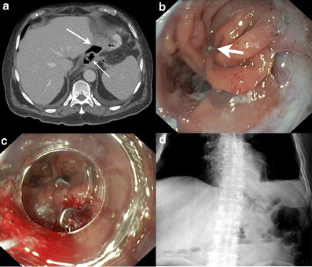

Fig. 1